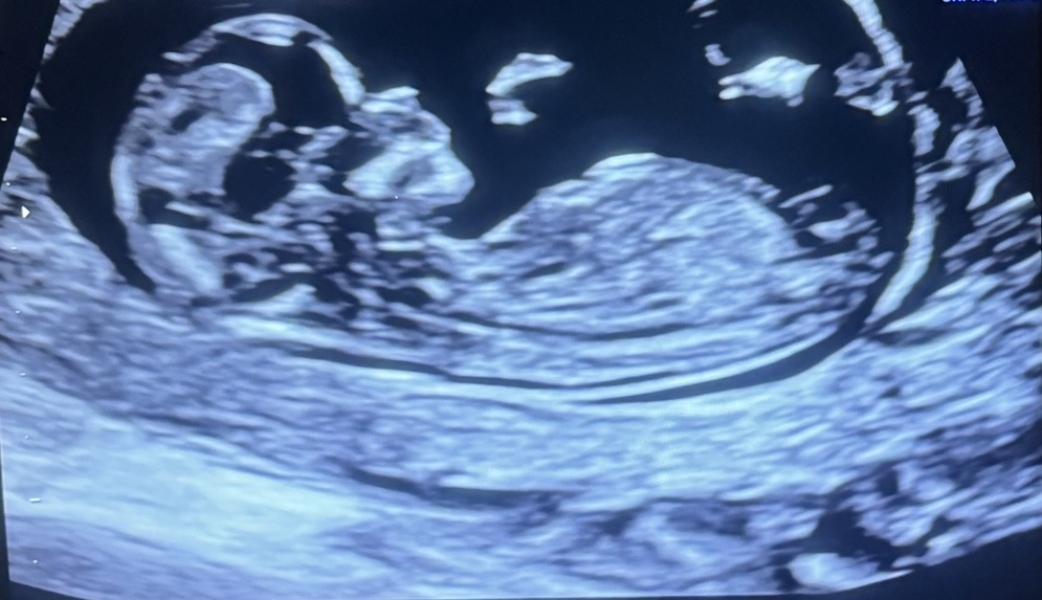

I am expecting a child and I wanted to know if it’s a girl or a boy through nub theory. What do you think? :)